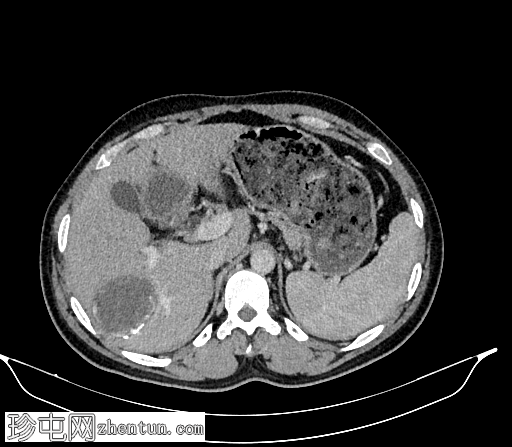

冠状位增强扫描(门静脉期)

4.jpg

肝脏VII段可见一边界清晰的囊性病变,内部有分隔,囊壁可见钙化。

右肾中央部分(肾门)可见一囊性病变,中心可见基质,周围可见子囊。该病变与肾盂肾盏无交通。病变周围可见两处高密度影,位于上、中肾盏,无法区分是结石还是病变壁钙化。另可见上极肾盏中度扩张。

影像学特征提示肝脏和右肾包虫囊肿。